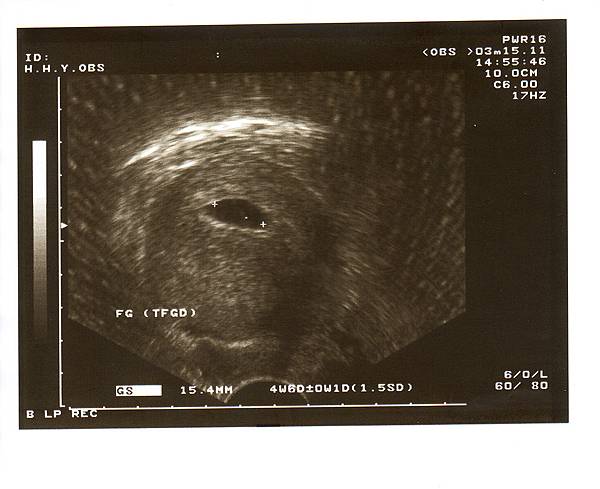

2011.03.15 確定寶寶安穩地在子宮內著床並且持續長大中